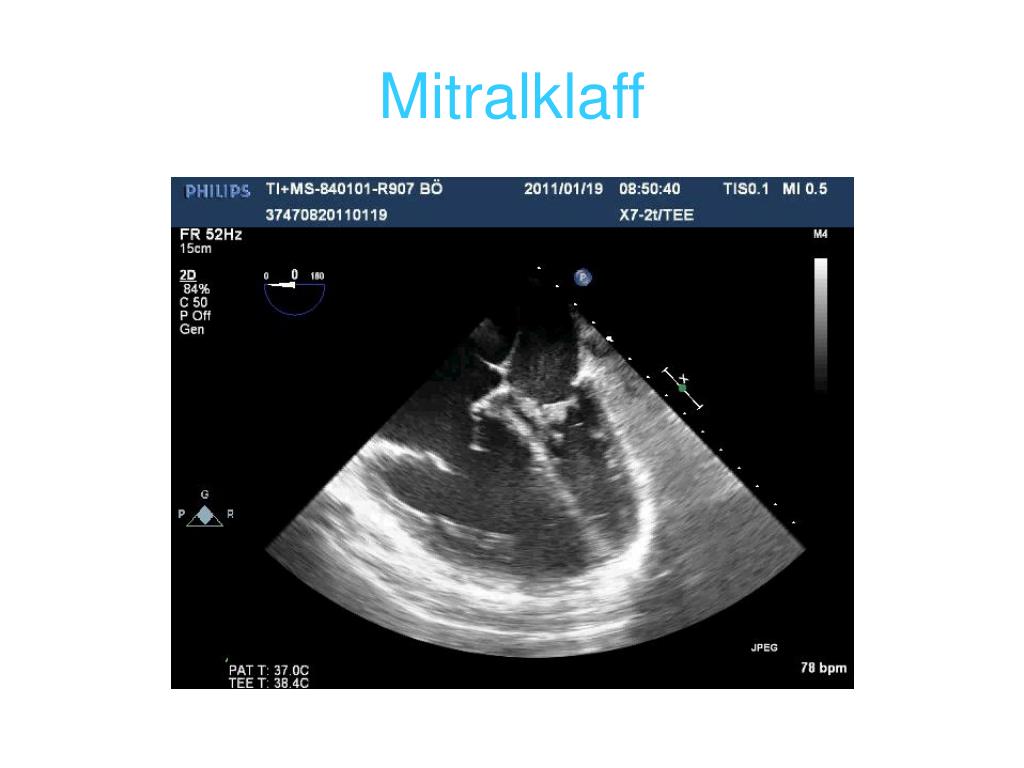

30. Mitralklaff

31. Mitralisklaff